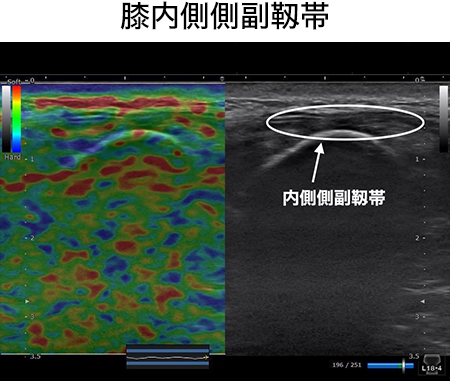

この弓状膝窩靭帯を治療したことはありますか?この靭帯は腓骨頭の外側面から膝窩筋腱を横切って、関節包に付着しています。このように関節包に付着するということは当然関節包に刺激を加え、痛みを生じさせます。そして関節包自体もしくは隣接する膝窩筋に対しても滑走性の低下、筋高度を高めてしまいます。膝痛の最終調整には欠かせない靭帯調整リリーステクニックとなります。

この弓状膝窩靭帯リリーステクニックを学ぶことであなたは、、、